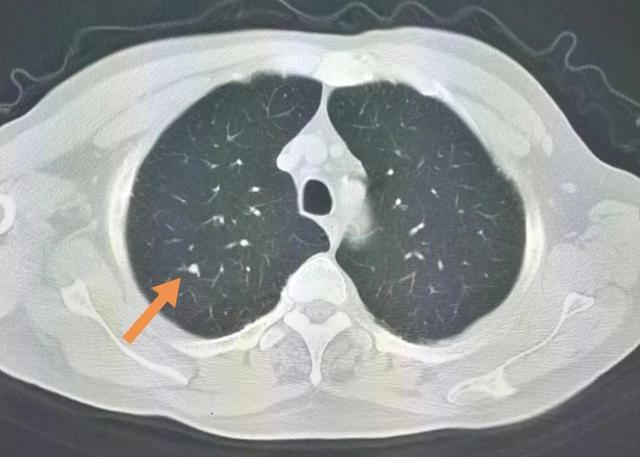

主要表现咳嗽,少许灰痰,无发热等毒性症状,胸部ct示右下肺类圆形结节